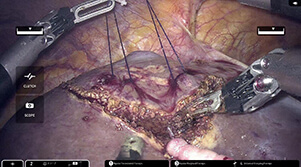

開腹 腹腔鏡 ロボット 合計 鏡視下% 2024 34 62 28 124 73% 2023 47 78 14 139 66% 2022 32 66 0 98 67% 2021 30 91 0 121 75% 2020 35 83 0 118 70% 2019 69 65 0 134 49% 2018 42 64 0 106 60% 2017 49 71 0 120 59% 2016 97 37 0 134 28% 2015 92 12 0 104 12% 2014 80 13 0 93 14% 2013 82 7 0 89 8% 2012 83 6 0 89 7% 2011 101 5 0 106 5% 【図4】腹腔鏡術中写真

【図5】ロボット手術術中写真da Vinci

hinotori

ロボット手術写真